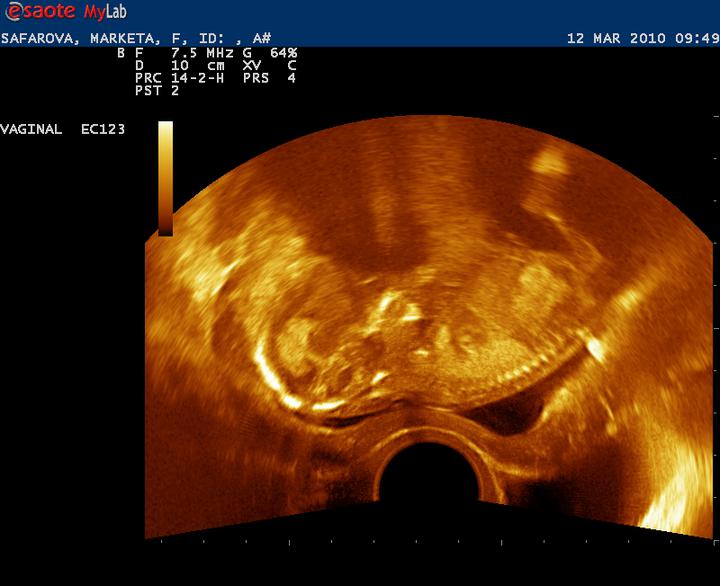

Už na druhé kontrole jsem otevřená na prst a čípek skoro žádný (v průkajdě H1). Prý už budeme brzy rodit a na další kontrolu nedojdeme 🙂. Zatím to tak ale nevypadá, cítím se úplně normálně...